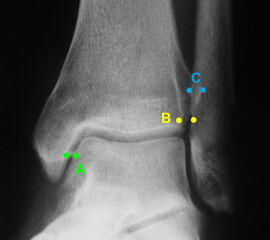

Röntgenaufnahmen dienen primär dem Ausschluss einer knöchernen Verletzung. Die Beurteilung der Geometrie der Malleolengabel kann einen ersten Hinweis auf eine Syndesmosenverletzung liefern. Die notwendigen Röntgenaufnahmen umfassen das Sprunggelenk anterior-posterior, lateral und in 20° Innenrotation (Mortise view). Zur Beurteilung der Syndesmose sind verschieden Parameter in der Mortise view beschrieben. Zu diesen zählen der tibiofibulare Clearspace, der mediale Clearspace, sowie die Überlappung der distalen Fibula und Tibia im Bereich der Incisura (Abbildung 2). Der Tibiofibulare Clearspace wird als verlässlichster Indikator für eine Syndesmosenverletzung gesehen, da er nicht signifikant von der tibialen Rotation beeinflusst wird 32. Er wird 1 cm proximal des Tibiaplafonds gemessen und sollte weniger als 6mm betragen 33. Jede Messung, die diesen Wert übersteigt, stellt einen Hinweis für eine Syndesmosenverletzung dar. Eine tibiofibulare Überlappung von 6 mm oder mehr in der AP Aufnahme, sowie mehr als 1 mm in der Mortise View Aufnahme gelten als physiologisch 33. Der mediale Clearspace sollte nicht mehr als 4 mm betragen 34.

Abbildung 3 zeigt ein Sprunggelenk nach Syndesmosenverletzung mit einem erweiterten Tibiofibularen Clearspace.